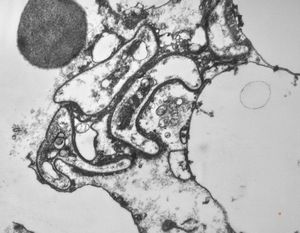

M,50y. | Pneumocystis carinii - lung